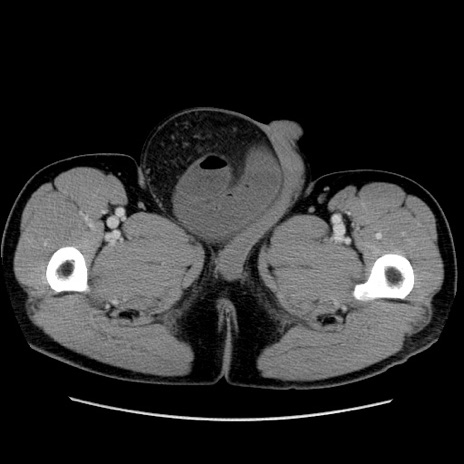

症例34(横断像)

【症例】60歳代 男性

【主訴】右鼠径部膨隆

【現病歴】1年程前より右鼠径部膨隆あり。自己にて還納可能だったため放置していた。3時間前より右鼠径部の脱出を認め、還納困難となり受診。

【既往歴】高血圧

【身体所見】右鼠径部に小児頭大の膨隆あり。弾性硬であり、用手還納は困難。左鼠径部にも膨隆を認める。脱出はなし。

【データ】WBC 15500、CRP 測定なし